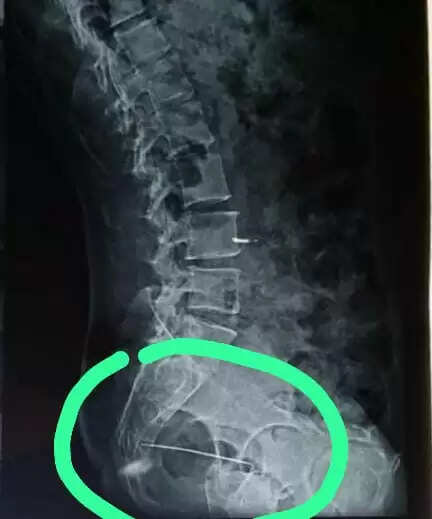

जटिल सर्जरी: रीढ़ व कूल्हे के बीच धंसी 6 सेंटीमीटर की सुई सफलतापूर्वक निकाली

अजमेर, 31 जुलाई(हि.स.)। अजमेर के चिकित्सकों ने एक अत्यंत जटिल और जोखिमपूर्ण सर्जरी को सफलतापूर्वक अंजाम देकर 43 वर्षीय महिला को राहत दी है। महिला की रीढ़ की हड्डी और कूल्हे के बीच गहराई में धंसी हुई 6 सेंटीमीटर लंबी सुई को मित्तल हॉस्पिटल एंड रिसर्च सेंटर के ब्रेन व स्पाइन सर्जन डॉ ए. आर गौरी एवं आर्थोपेडिक सर्जन डॉ दीपक जैन की अगुवाई में चिकित्सकों की टीम ने जटिल सर्जरी के बाद सुरक्षित रूप से बाहर निकाला।

पीड़ित महिला रामगंज क्षेत्र की निवासी हैं, जो पहले भी हार्ट सर्जरी से गुजर चुकी हैं और कमर के नीचे के हिस्से में शिथिलता की समस्या से जूझ रही थीं। कुछ समय से उन्हें नींद में भी असहनीय पीड़ा हो रही थी, जिससे चिंतित परिजनों ने प्रारंभिक तौर पर इसे बिस्तर पर लेटे रहने के कारण उत्पन्न बेडसोर समझा। बाद में बैठने की अवस्था में अत्यधिक पीड़ा होने पर पीड़ित को रेलवे हॉस्पिटल के ऑर्थोपेडिक विभाग में दिखाया गया। रेलवे हॉस्पिटल में हुई जांच में यह चौंकाने वाला तथ्य सामने आया कि रीढ़ और कूल्हे के बीच सुई धंसी हुई है।

रेलवे हॉस्पिटल ने उन्हें उच्च चिकित्सा सुविधा की सलाह दी, जिसके बाद मरीज को मित्तल हॉस्पिटल रेफर किया गया। वरिष्ठ ब्रेन व स्पाइन सर्जन डॉ. ए.आर. गौरी ने कार्डियोलॉजिस्ट डॉ. राहुल गुप्ता, आर्थोपेडिक सर्जन डॉ. दीपक जैन, रेडियोलॉजिस्ट डॉ. गरिमा खींची एवं डॉ. प्रगति गक्खड़ के साथ गहन विचार.विमर्श कर सर्जरी की योजना बनाई।

डॉ. गौरी ने बताया कि पीड़िता बचपन से हार्ट पेशेंट होने के साथ.साथ निचले शरीर की कमजोरी से पीड़ित हैं, जिससे यह ऑपरेशन और भी जोखिमपूर्ण हो गया था। ऑपरेशन से पूर्व महिला की सभी आवश्यक जांचें करवाई गईं और फिर पूरी सावधानी व सटीकता के साथ सुई को निकाला गया।

सर्जरी के सफलतापूर्वक संपन्न होने के बाद महिला अब पूरी तरह स्वस्थ हैं और उन्हें अस्पताल से छुट्टी दे दी गई है। जांच में सामने आया कि महिला घर पर सिलाई.कढ़ाई का कार्य करती थीं और संभवतः बिस्तर पर पड़ी सूई करवट लेते समय शरीर में धंस गई, जिसका उन्हें पता तक नहीं चला।